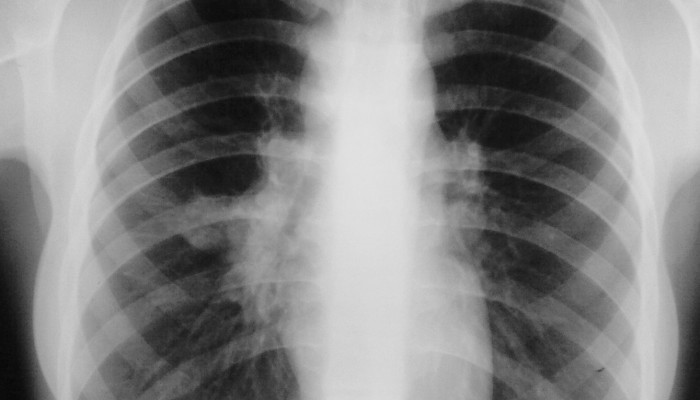

- Рентгенография легких и позвоночника.